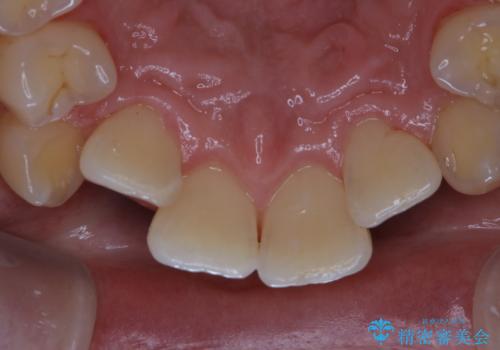

タバコのヤニをPMTCできれいに

- タバコによる着色が気になるため、全て取りたいとのことで来院されました。PMTC60分コースを行いました。

PMTCは、歯に付着した汚れを除去していくため、着色が気になる場合にも行うことができます。ご自身でのセルフケアだけで着色を落とそうとすると、逆に歯を傷つけてしまったり、精密に汚れを除去できないこともあります。また、日常生活で着色しやすい飲食物を避けたりすることはストレスに感じてしまったり、あまり現実的ではありません。

歯科医院にて、適切な処置を行うことで、長期的に安定したお口の環境が作られます。まずはカウンセリングなどもおススメです。